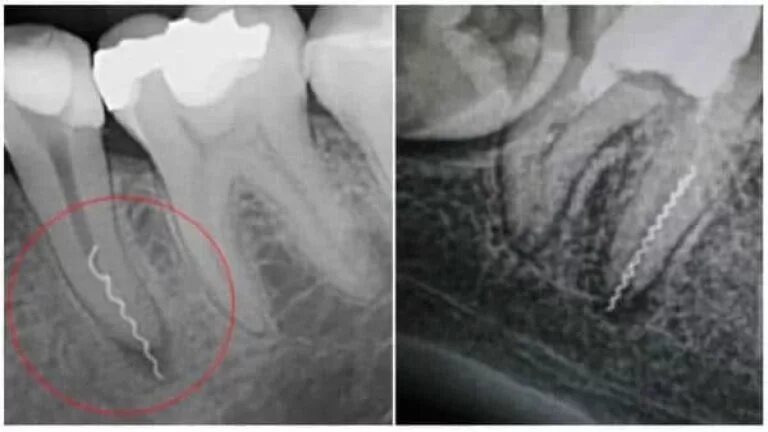

Отлом эндодонтического инструмента в канале корня. перелом корня зуба пломбировка. неполное пломбирование корневого канала. пломбировка верхушки корня рентген.

Перфорация корневого канала зуба. перфорации стенки корневого канала зуба. апикальная перфорация стенки корневого канала. перфорация корневого канала классификация.

Перфорация корневого канала зуба. перфорация корня зуба на рентгеновском снимке. перфорация корневого канала рентген. перфорации стенки корневого канала зуба.